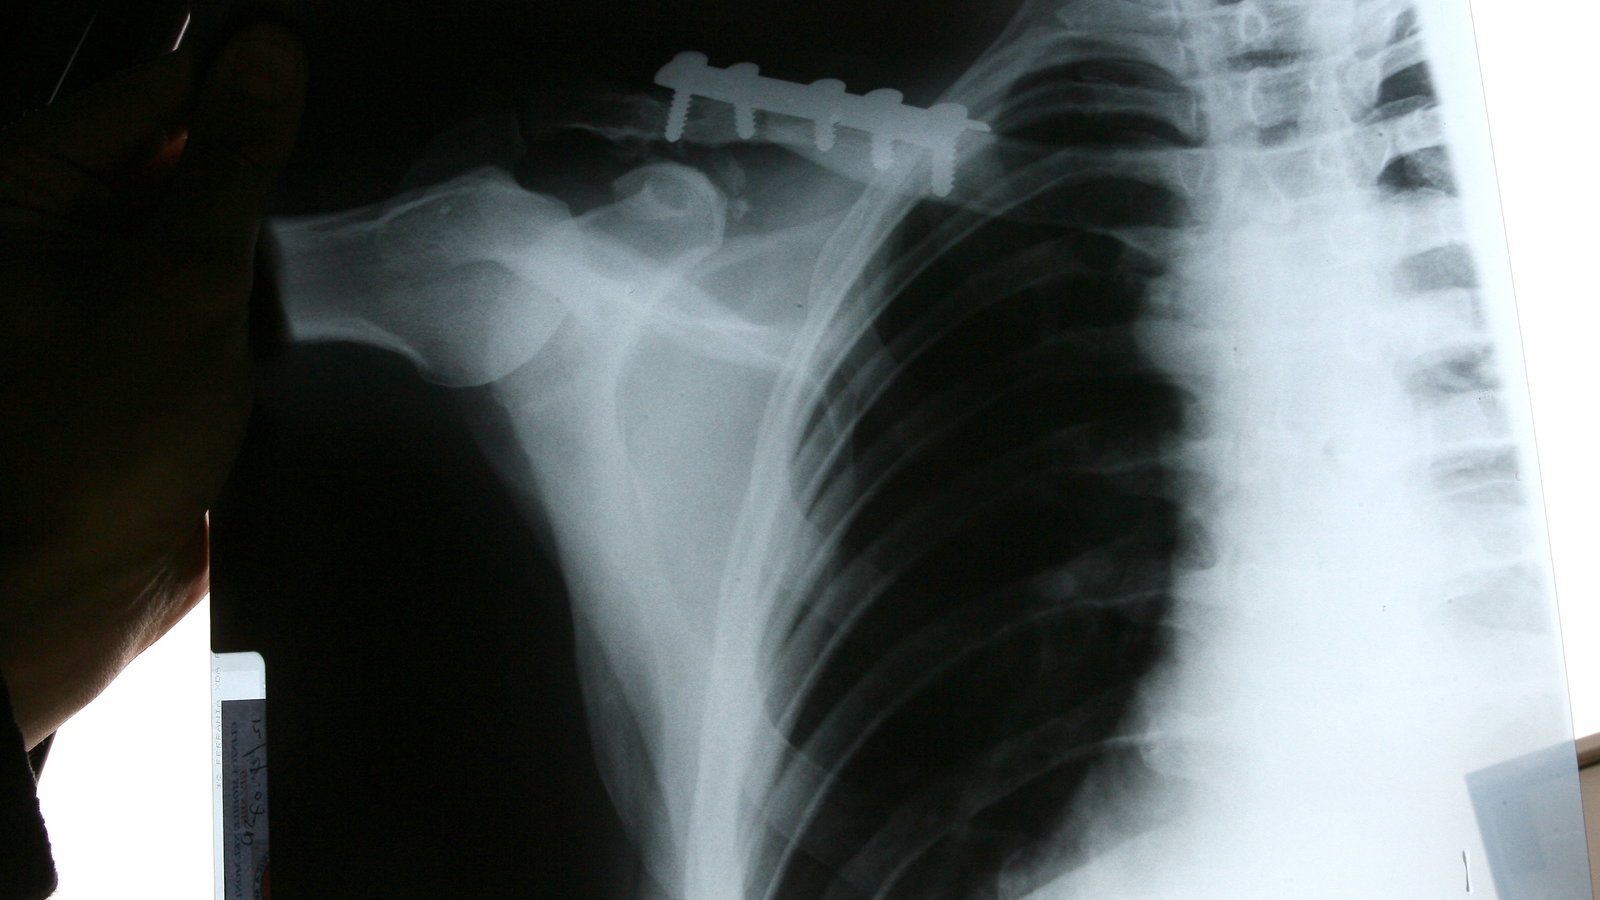

These x-rays show the latest metalwork inserted into the fractured collarbones of Yamaha World Supersport team-mates Broc Parkes (top and middle pictures) and Kevin Curtain after both were injured, at the same corner, during Friday free practice at Donington Park two weeks ago.

Both Australians underwent surgery following their accidents and were hoping to ride this weekend at Valencia, but both missed Friday morning's first practice session...